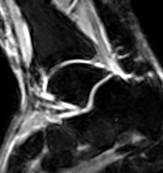

При МР-томографии интенсивность сигнала задней малоберцово-таранной связки повышена на Т2 ВИ, контуры прерывисты.

| Рис 2. Аксиальная и коронарная плоскости сканирования. Т2 ВИ. Стрелкой показан полный разрыв задней малоберцово-таранной связки. В коронарной плоскости (б) можно лишь предположить наличие повреждения, а на аксиальной (а) это полностью подтверждено. | ||||